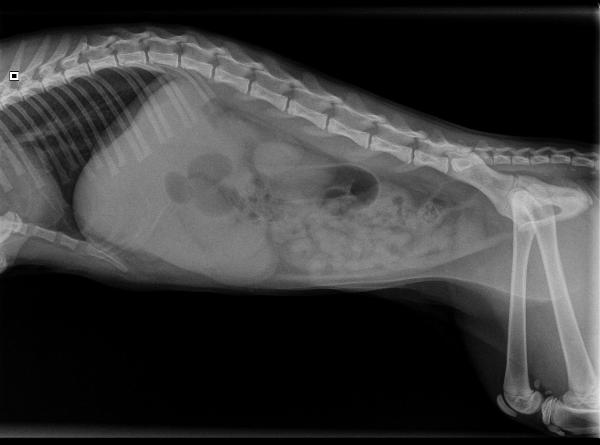

De volgende dag is Balou eerder zieker dan beter geworden. Het braken is dan wel gestopt, maar de buikpijn is verergerd. We besluiten een röntgenfoto te maken om meer informatie te krijgen over de oorzaak. Op de röntgenfoto zijn we vooral een erg onrustige darm. De hele darm is leeg en er zijn gebieden waar veel gas zichtbaar is. Bij het klinisch onderzoek denken we iets hards te voelen in de buik, maar goed voelen valt bij zo'n gespannen buikje nog wel eens tegen.

Balou's buik op de röntgenfoto